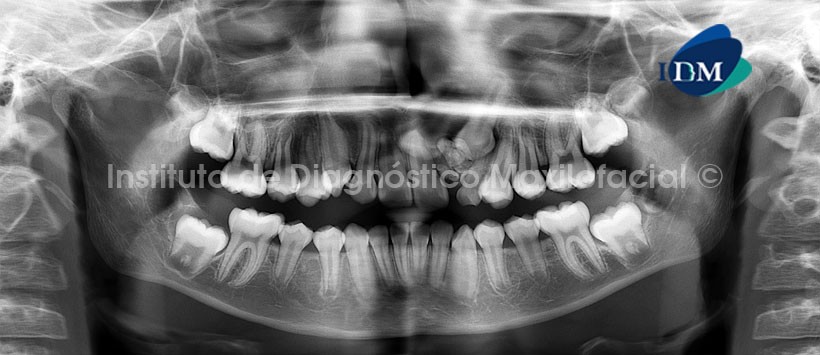

Radiográficamente se localiza entre las raíces dentarias, y se observa como una masa radiopaca, usualmente irregular, dentro de la que se pueden reconocer los dientes; a veces limitada por una línea radiolúcida que representa el espacio pericoronario del diente no erupcionado.